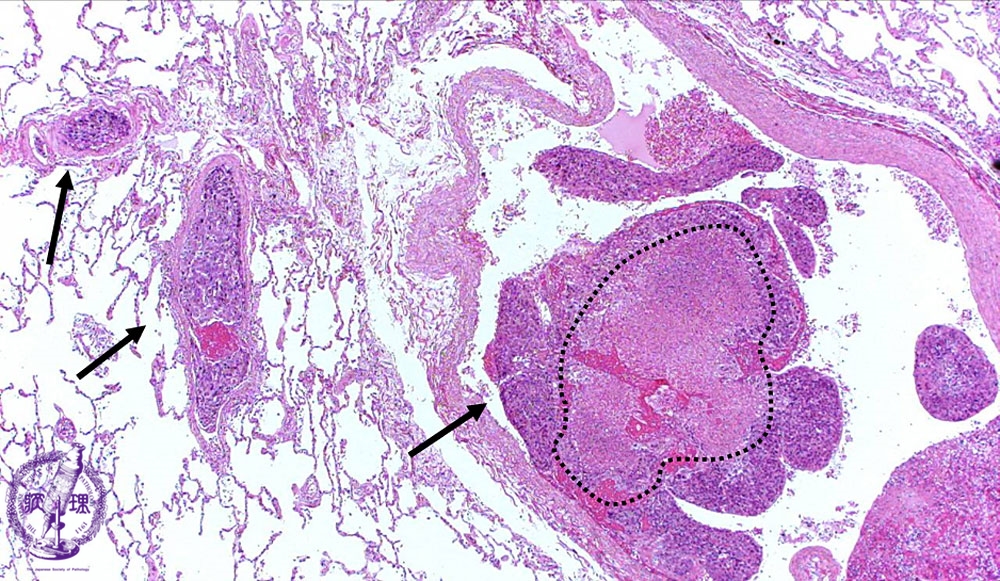

Microscopic view (HE stain, low power view): Large tumor emboli are seen within the pulmonary artery lumen (arrow). There is associated necrosis (dotted line).